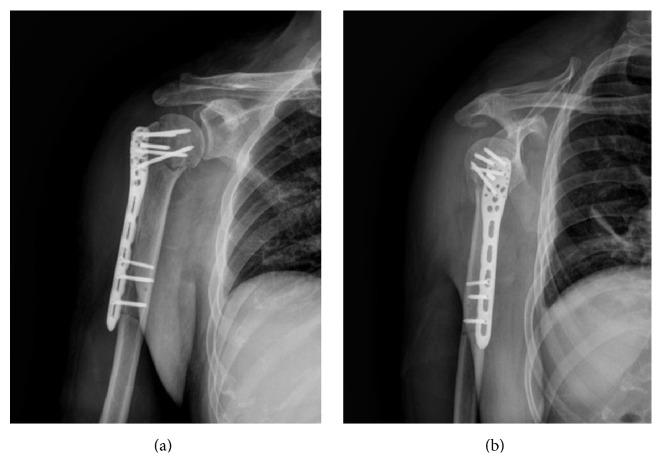

There is a growing concern about elderly valgus impacted proximal humeral fractures. The aim of this study was to evaluate the treatment and clinical outcomes following minimal invasive percutaneous plate osteosynthesis (MIPPO) with the proximal humeral internal locking system (PHILOS) for the treatment of elderly valgus impacted proximal humeral fracture. Between May 2008 and May 2012, 27 patients (average age 67.3, range 61-74) with valgus impacted proximal humeral fractures were enrolled in the study. The patients were treated with MIPPO using PHILOS-plate through the anterolateral delta-splitting approach. Rehabilitation exercises were done gradually. The NEER score and Constant-Murley score were used to evaluate shoulder function. All the patients were followed up by routine radiological imaging and clinical examination. There were 15 cases of II-part greater tuberosity fractures, 10 cases of III-part greater tuberosity fractures, and 2 cases of IV-part fractures according to the NEER classification. The surgery was successful in all patients with an average follow-up of 20.8 (range: 11-34) months. The fractures united in an average of 7.2 (6-14) weeks without implant loosening. According to NEER score, there were 17 excellent, 7 satisfactory, 2 unsatisfactory, and 1 poor. The mean Constant-Murley score was 89.4 ± 4.35. No complication including axillary nerve damage, postoperative nerve or vessel damage, infections, DVT, or death was observed. In conclusion, the MIPPO technique with the PHILOS through the anterolateral delta-splitting approach seems to be a safe and easy treatment for elderly valgus impacted proximal humeral fractures. A case-control study and longer follow-up time are needed.

老年肱骨近端外翻嵌插骨折越来越受到关注。本研究的目的是评估采用肱骨近端内锁定系统(PHILOS)的微创经皮钢板接骨术(MIPPO)治疗老年肱骨近端外翻嵌插骨折的治疗方法及临床疗效。2008年5月至2012年5月,27例(平均年龄67.3岁,范围61 - 74岁)肱骨近端外翻嵌插骨折患者纳入本研究。采用经前外侧三角肌劈开入路,使用PHILOS钢板行MIPPO治疗这些患者。康复锻炼逐步进行。采用NEER评分和Constant-Murley评分评估肩关节功能。所有患者均通过常规影像学检查和临床检查进行随访。根据NEER分类,有15例二部分大结节骨折,10例三部分大结节骨折,2例四部分骨折。所有患者手术均成功,平均随访20.8(范围:11 - 34)个月。骨折平均在7.2(6 - 14)周愈合,无植入物松动。根据NEER评分,优17例,良7例,可2例,差1例。Constant-Murley平均评分为89.4 ± 4.35。未观察到包括腋神经损伤、术后神经或血管损伤、感染、深静脉血栓形成(DVT)或死亡等并发症。总之,采用经前外侧三角肌劈开入路的PHILOS行MIPPO技术似乎是治疗老年肱骨近端外翻嵌插骨折安全且简便的方法。需要进行病例对照研究和更长时间的随访。